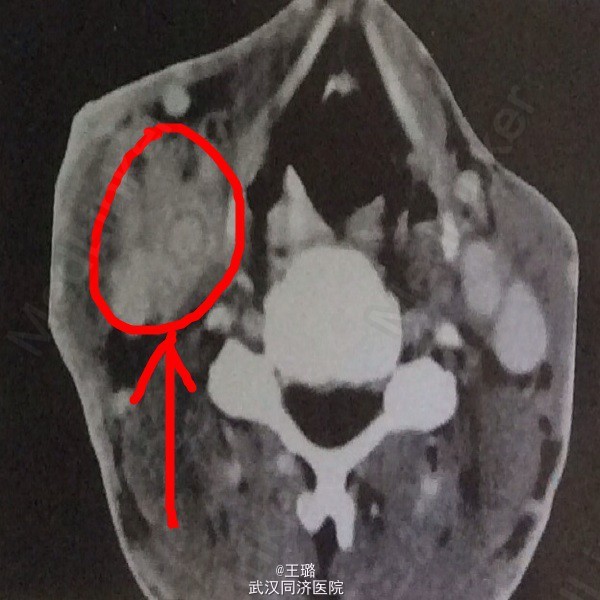

患者,男,37岁,发现右颈部肿物、眼睑下垂一月入院。体检可闻及颈部血管杂音,眼睑下垂,面部表情淡泊,高血压。实检:电解质正常,白蛋白降低,血肌酐正常。颈部CT示:右颈部颈动脉分叉处见卵圆形软组织占位,密度不均匀,周围组织和器官有受压。增强CT:肿块明显强化,与动脉强化程度相仿。遂给予手术治疗,病检示:颈动脉瘤。其为发生于颈动脉体化学感受器的肿瘤,多为良性,压迫血管可闻及杂音,压迫颈交感神经可出现Horner综合征。